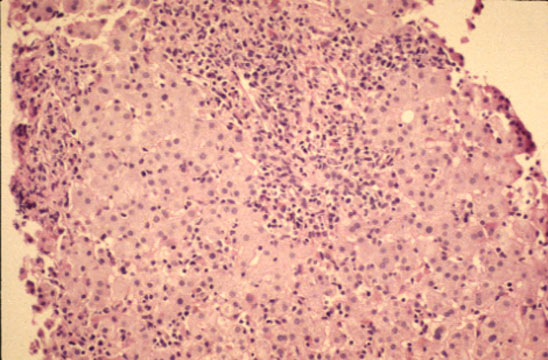

Diffuse lobular inflammation

Fig 53 - DIFFUSE LOBULAR INFLAMMATION: Diffusely scattered mononuclear cell infiltration of the lobule especially in the perivvenular area. Lymphocytes and monocytes predominate but neutrophils, eosinophils and plasma cells may be present.